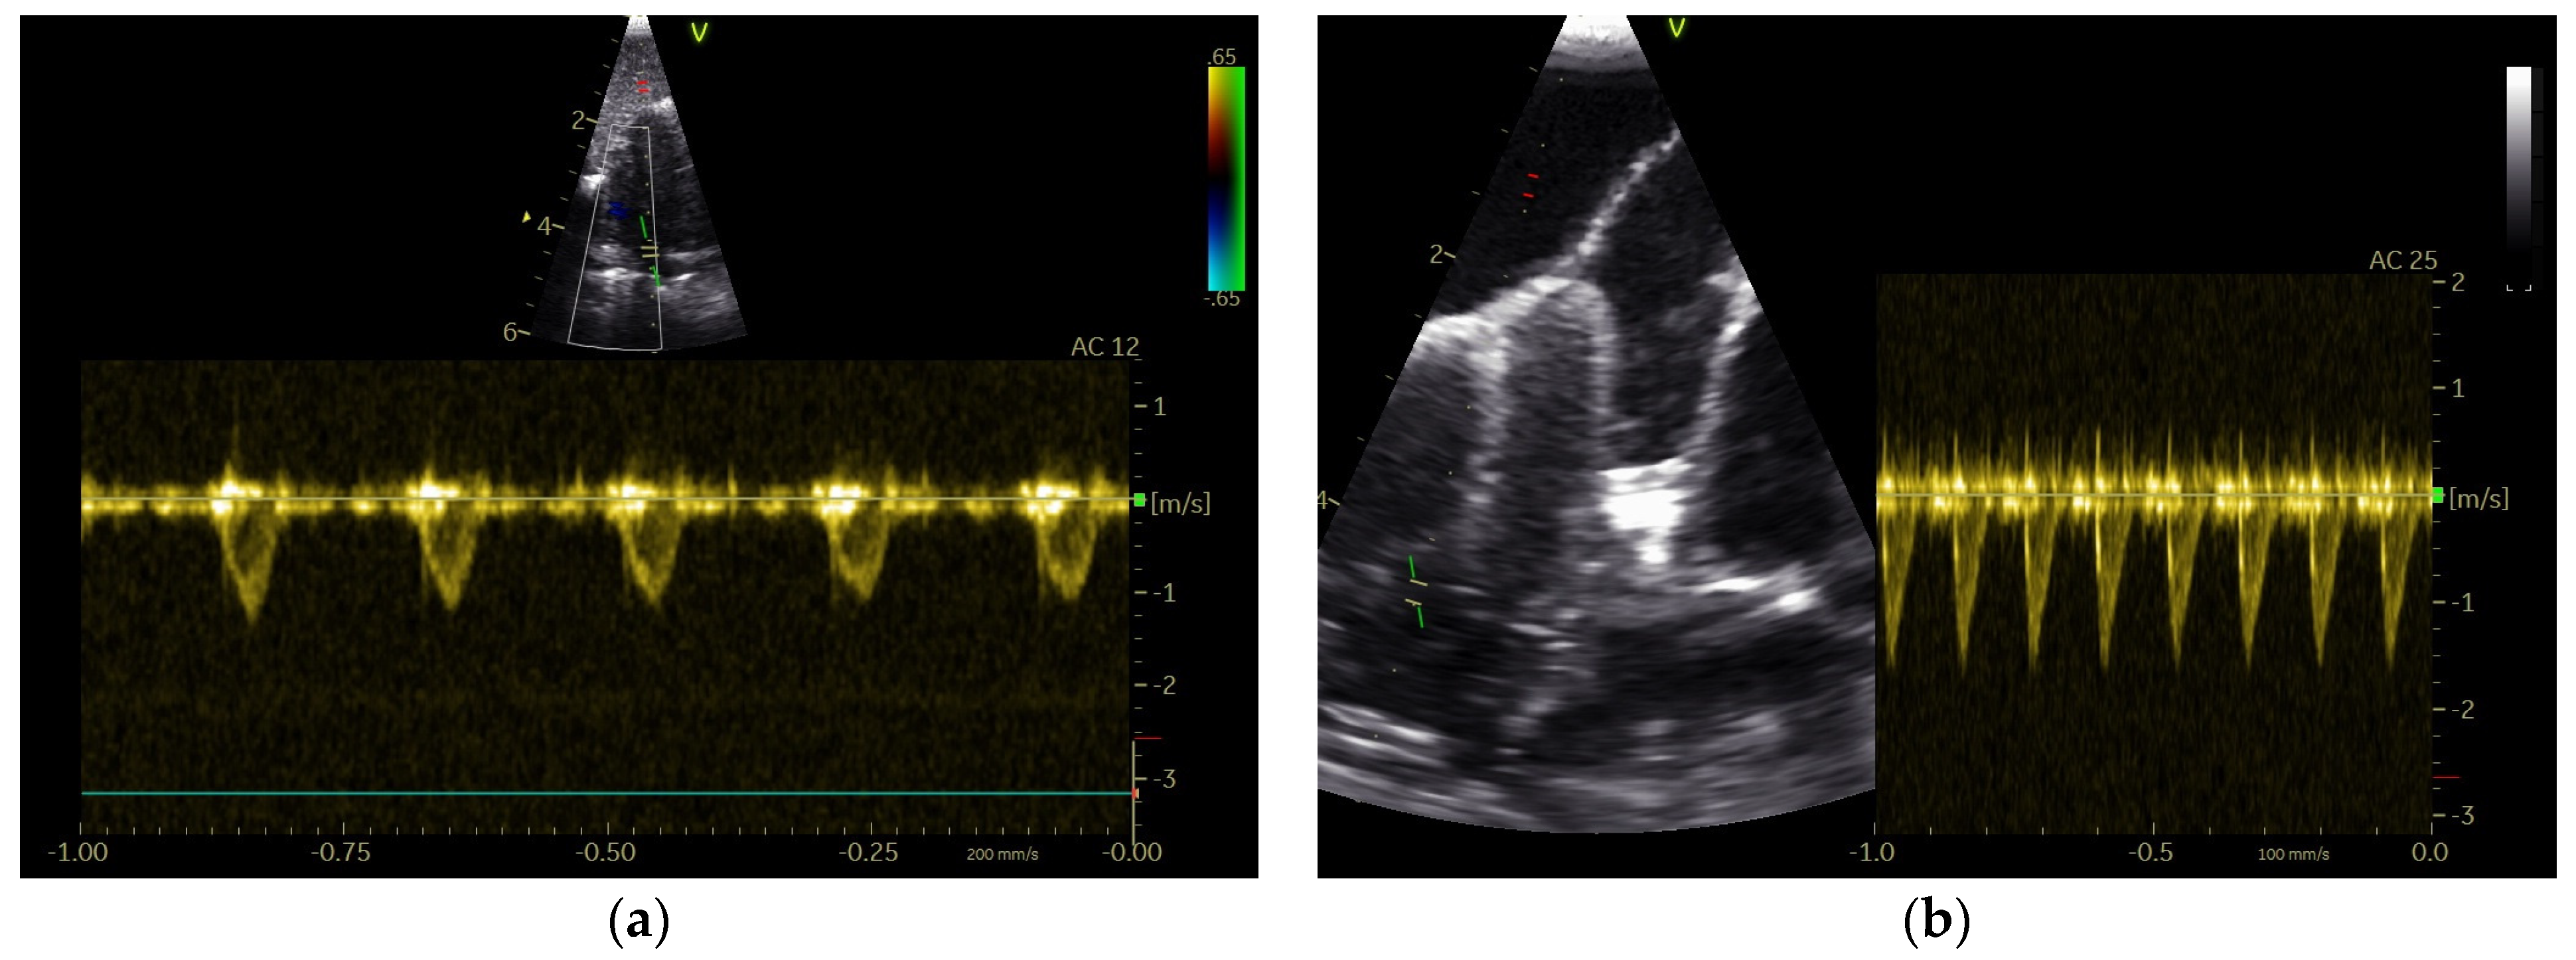

Abstract

2.2. Doppler Sonographic Examination

2.4. Measurements of the Doppler Blood Flow Profile

3.1. Shape of PAFP and AOFP